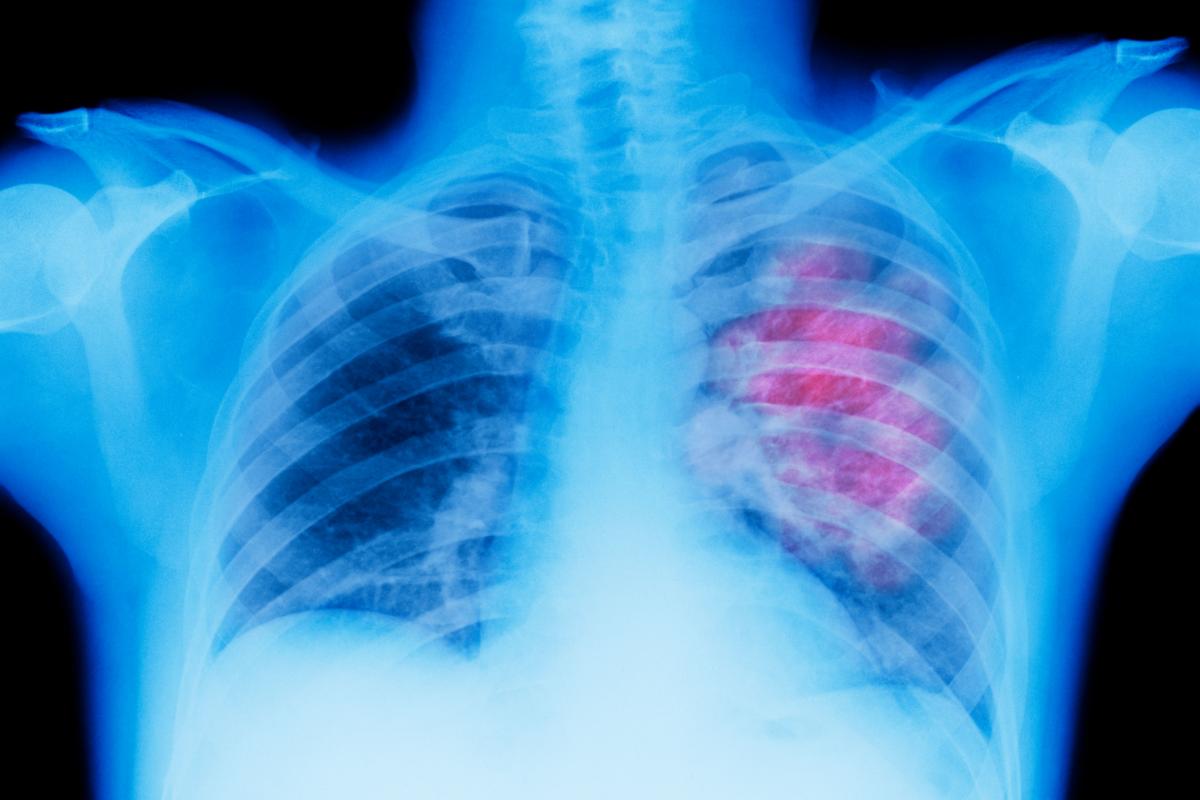

Un estudio español cambia el paradigma para tratar el cáncer de pulmón precoz

Una investigación del Grupo Español de Cáncer de Pulmón (GECP) ha ratificado el cambio de paradigma en el abordaje de estos tumores en estadios iniciales, sin metástasis, con una estrategia terapéutica que aumenta hasta el 93 % los pacientes candidatos a cirugía y logra erradicar el tumor en el 36,8 % de los casos, lo que favorece el proceso de curación.